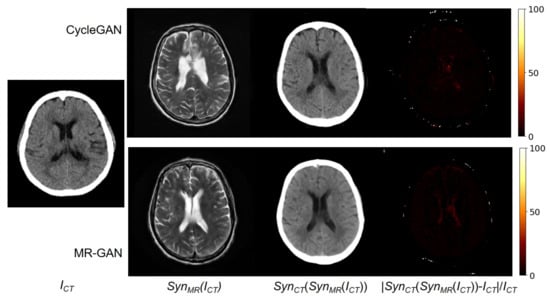

During the training of the MR-GAN, dual cycle-consistency loss is explicitly imposed in a bidirectional manner. Hence, an input CT image estimated to an MR image by the model should be successfully estimated back to the original CT domain. Figure 7 shows an input CT image, and the corresponding synthesized MR images from the CycleGAN and MR-GAN. It also shows their reconstructed CT images and their relative difference maps. It is observed that the reconstructed CT images are very close to the input images. The relative differences are distributed at the contour of the bone, and the reconstructed CT image from MR-GAN is apparently more smoothed than that from the CycleGAN model. This is because of the correct S y n M R ( I C T ) , which is like a latent vector in an auto-encoder [35].

Figure 7. From (left) to (right): Input CT image, synthesized MR image, reconstructed CT image, and relative difference error between the input and reconstructed CT images.